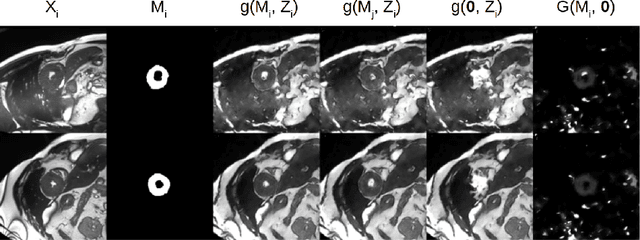

Abstract:The success and generalisation of deep learning algorithms heavily depend on learning good feature representations. In medical imaging this entails representing anatomical information, as well as properties related to the specific imaging setting. Anatomical information is required to perform further analysis, whereas imaging information is key to disentangle scanner variability and potential artefacts. The ability to factorise these would allow for training algorithms only on the relevant information according to the task. To date, such factorisation has not been attempted. In this paper, we propose a methodology of latent space factorisation relying on the cycle-consistency principle. As an example application, we consider cardiac MR segmentation, where we separate information related to the myocardium from other features related to imaging and surrounding substructures. We demonstrate the proposed method's utility in a semi-supervised setting: we use very few labelled images together with many unlabelled images to train a myocardium segmentation neural network. Specifically, we achieve comparable performance to fully supervised networks using a fraction of labelled images in experiments on ACDC and a dataset from Edinburgh Imaging Facility QMRI. Code will be made available at https://github.com/agis85/spatial_factorisation.